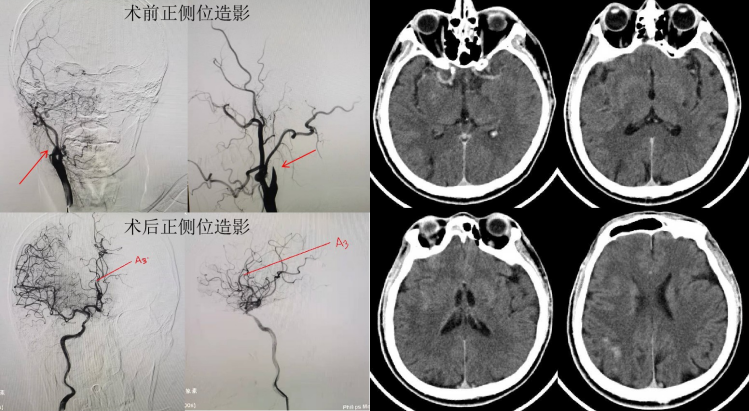

联系卒中中心介入组后,神经内科专家副院长刘忠锦、王雷主治医师及王晓宇医师迅速到达导管室,行全脑血管造影证实为“右侧颈内动脉闭塞”。与家属沟通并获得同意后全麻下行机械取栓术,在麻醉科、介入导管室医护人员的全力配合下,历时两个小时,手术圆满成功。

经过神经内科14天的努力治疗,病人恢复非常好,出院时各项功能基本恢复正常。孟大爷的女儿感激地说:“发病时不省人事,现在能说、能笑了,胳膊腿能正常活动,简直是不可思议,多亏了刘忠锦院长和他的取栓团队了”。